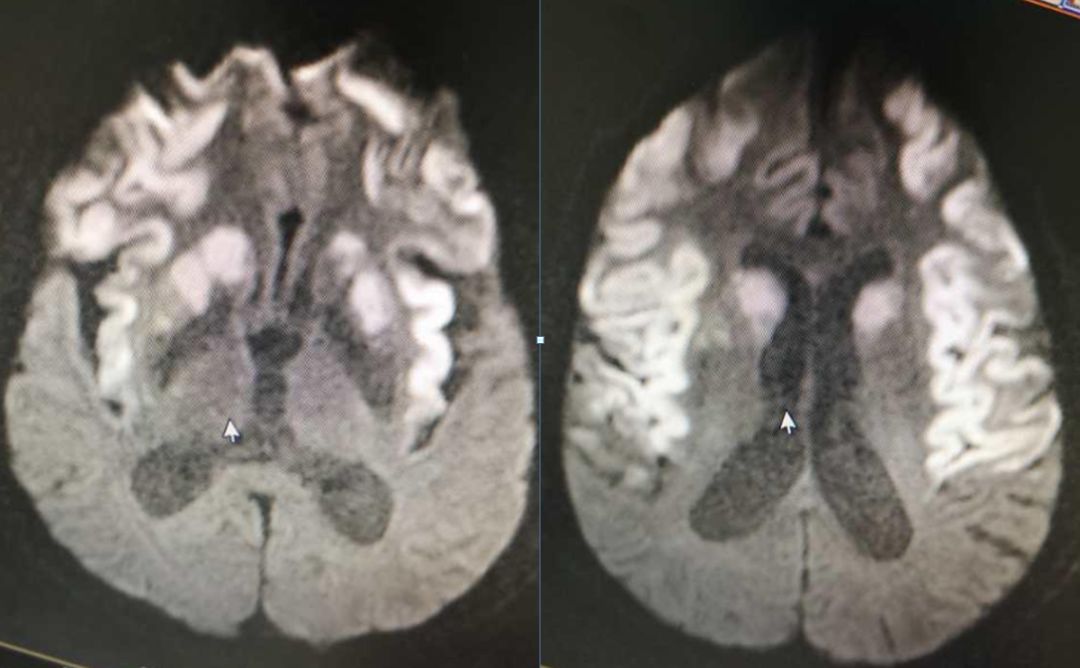

男,29岁,言语不清,协调不良以及行走不平衡3周。

答案:*洛因海**海绵状白质脑病。*洛因海**海绵状白质脑病(heroin spongiform leukoencephalopathy,HSLE)是因烫吸或静脉注射*洛因海**而引起的中枢神经系统器质性疾病。临床和影像特点如下:

1. 有吸*洛因海**史;

2. 急性或亚急性起病;

3. 小脑受损为首发症状,进一步加重可出现锥体系及锥体外系受损表现,甚至昏迷、去皮层态势,但感觉系统不受累;

4. CT和MRI影像显示病灶位于脑白质区,呈广泛、对侧性损害(小脑半球、脑干、内囊后肢、胼胝体压部及大脑半球后2/3),其中小脑受累严重,小脑中线两旁、边界清楚的对侧性类圆形或蝴蝶样病灶最具特点(蝶翼征);在脑干部位,若同时有红核及网状结构受累,则可见“蟹钳征”;在内囊后肢则呈“八字征”。病变在T1W为低信号,T2WI为高信号,FLAIR为高信号,且增强扫描一般无强化.5.病理显示脑白质空泡样变。